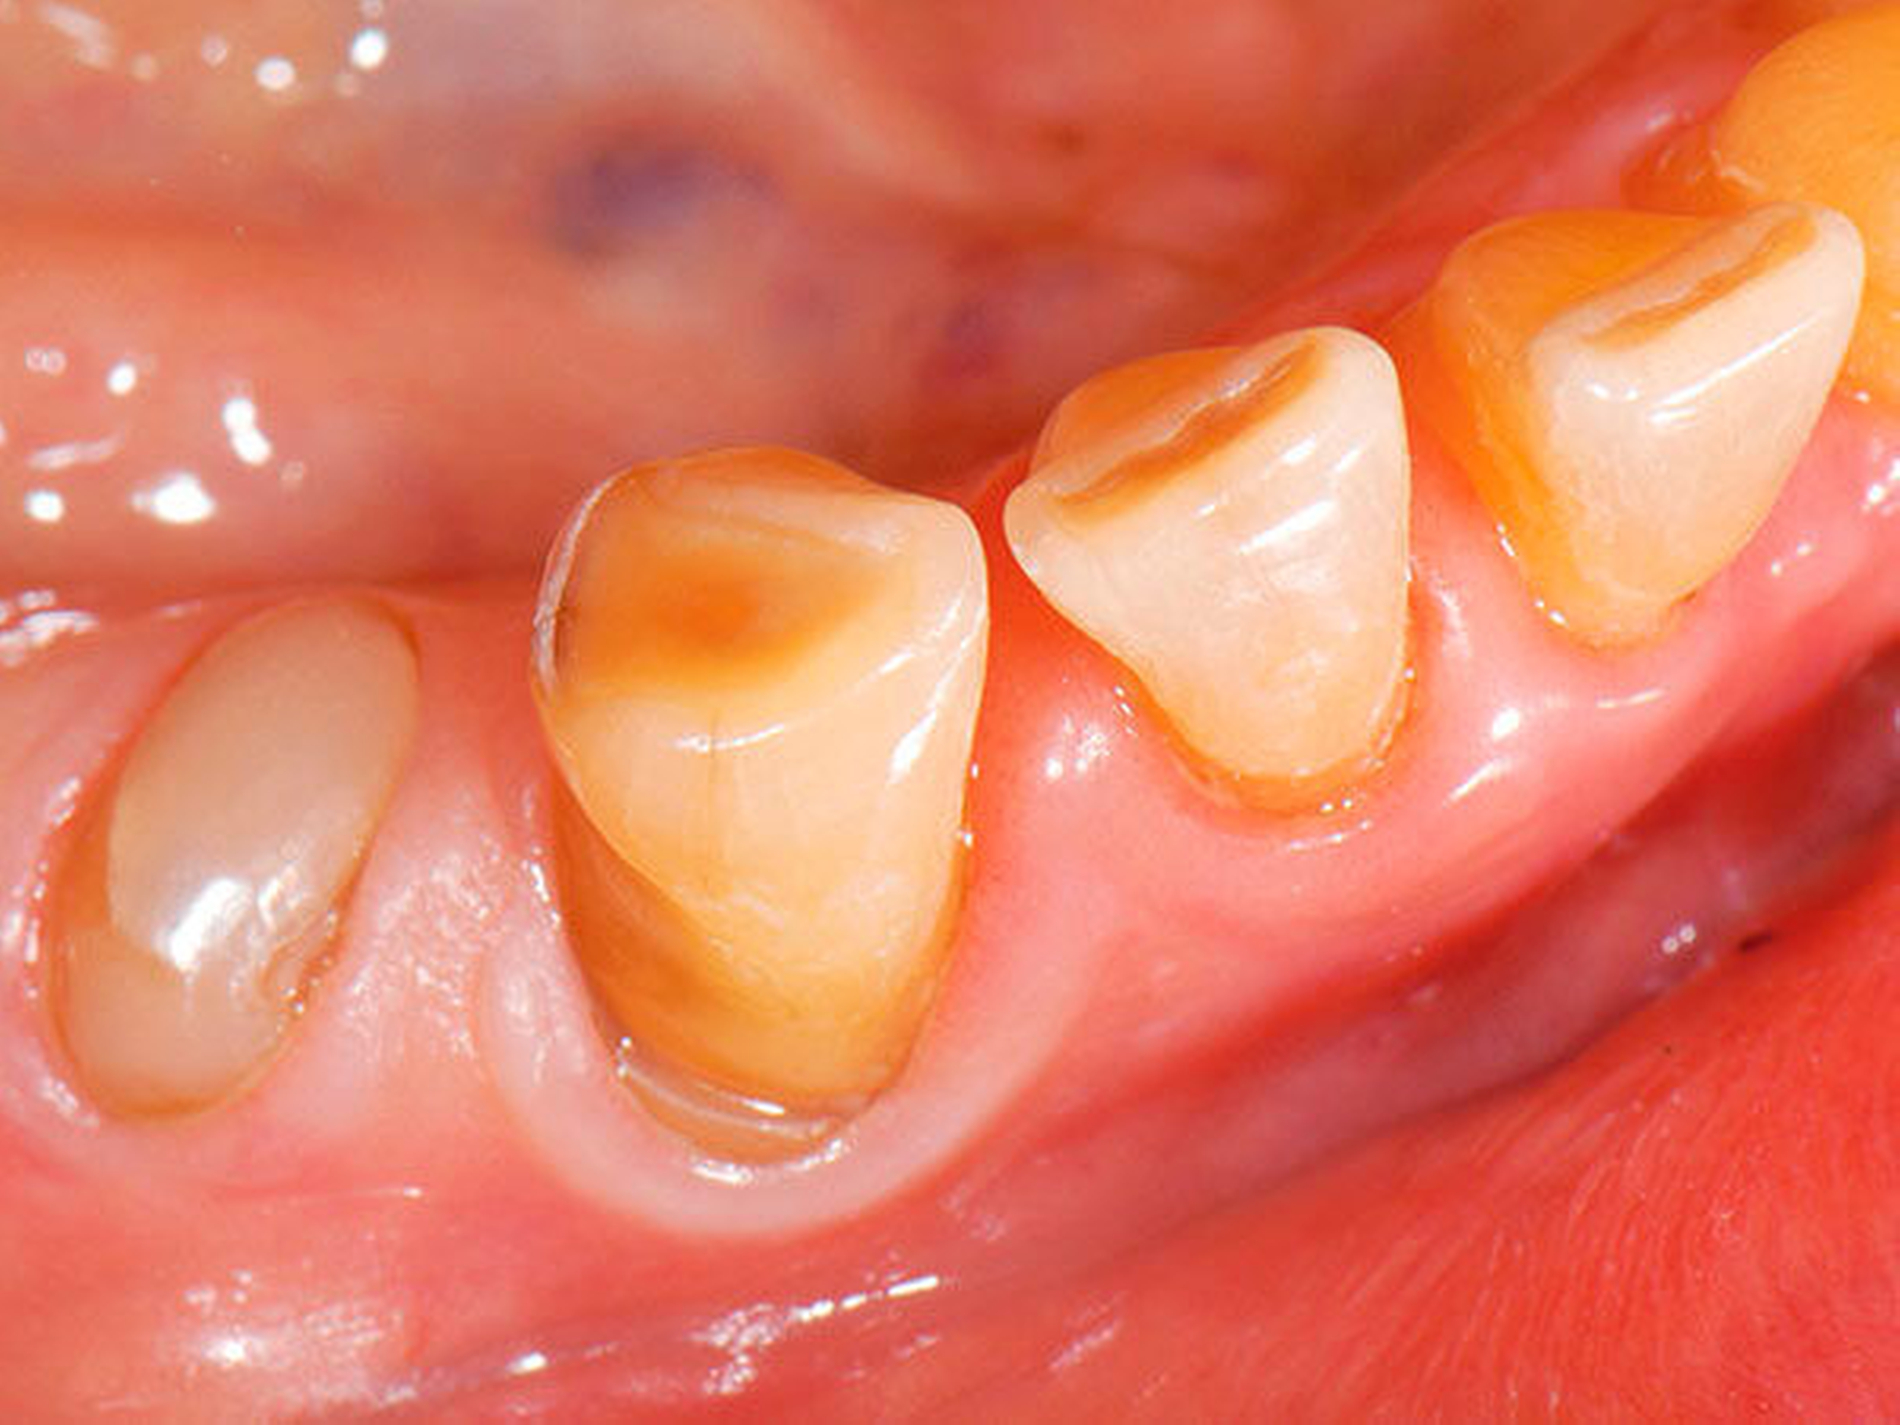

Üblicherweise werden frakturierte Zahnkronen beziehungsweise Wurzelreste restaurativ wieder aufgebaut oder es erfolgt eine Extraktion. Im Seniorenalter erscheint es hingegen manchmal als Kompromissmaßnahme vertretbar, Wurzelreste vorerst zu belassen und etwa mit adhäsiv eingebrachtem Komposit knapp über Gingivahöhe abzudecken. Dies bietet sich vor allem dann an, wenn die Wurzelkanäle bereits obliteriert und endodontische Interventionen nicht erforderlich sind (Tabelle 4) [Staehle et al., 2017].

Abbildung 4: Anliegen eines 76,5-jährigen Patienten (Anfrage per E-Mail). Zitat: „Mich plagt eine … Entzündung des Mundraums, die auch das Zahnfleisch meiner Zahnstummel angreift, weshalb ich nur noch Breiartiges zu essen vermag. Ein Angsthase wie ich geht zum Zahnarzt NUR unter dem Eindruck akuter Schmerzen!“

Damit wird die Hygienefähigkeit zumindest partiell verbessert und Spielraum für künftige Planungen und Vorgehensweisen unter besseren Bedingungen belassen. Das Procedere ist in den Abbildungen 4 und 5 beschrieben. Bei dem in Abbildung 4 vorgestellten Patienten lag eine Oralphobie im Seniorenalter vor. Die Verlaufsbeschreibung macht deutlich, dass selbst im fortgeschrittenen Alter eine Adaptation an zahnärztliche Interventionen im Einzelfall noch möglich ist.